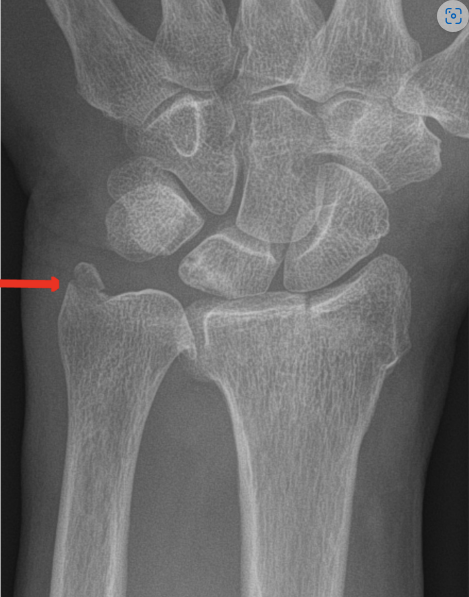

The given image shows a fracture of the styloid process of radius which is called a _____ fracture. (Ignore the red arrow)

In Colles # the distal segment is displaced _____ whereas in Smith # it is displaced volarly (dorsal/volar)